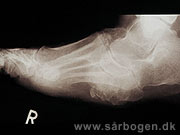

Charcot i mellemfod

Zoom

Charcot i mellemfod ...